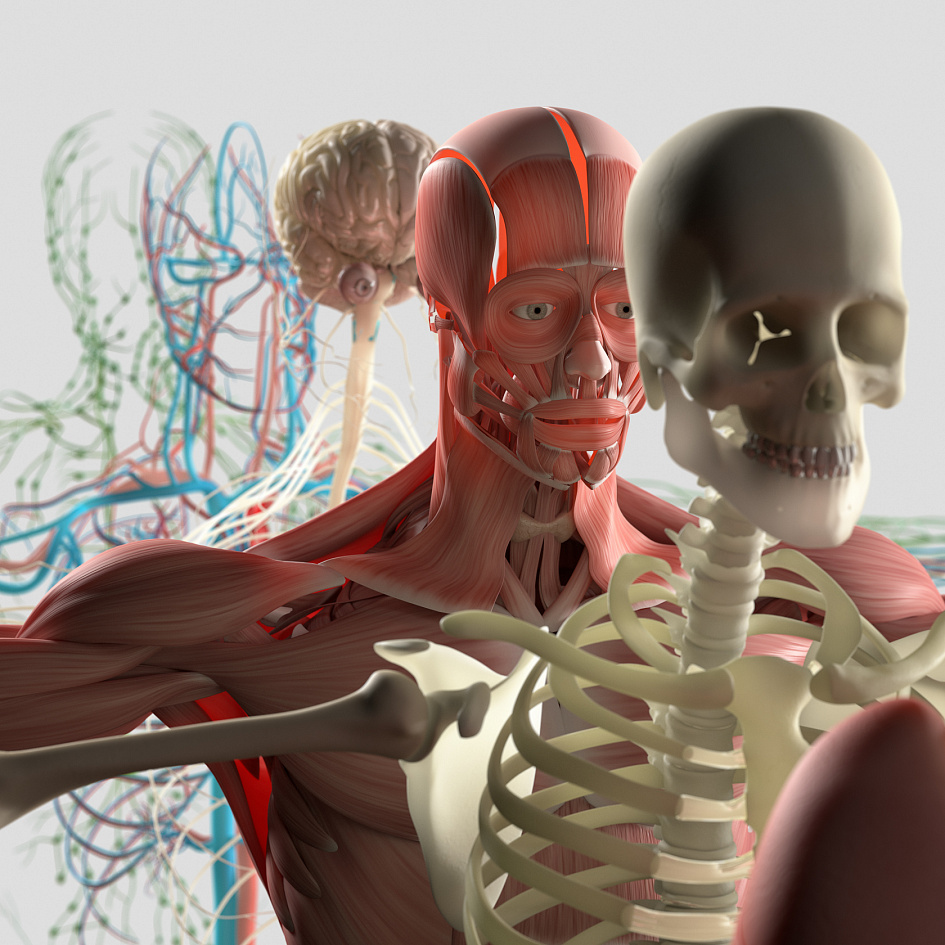

Строение человека: анатомия тканей и органов

Сходные по строению и функциям клетки в комплексе с межклеточным веществом образуют ткани, каждая из которых выполняет ряд определённых задач. В зависимости от этого в анатомии тела человека выделяют 4 группы тканей:

Комплекс тканей, локализованный в определённой части организма, имеющий чёткую форму и выполняющий общую функцию, является самостоятельным органом. Как правило, орган представлен различными типами клеток, однако, какой-то определённый вид ткани всегда преобладает, а остальные носят, скорее, вспомогательный характер.

В анатомии человека органы принято условно классифицировать на наружные и внутренние. Наружное, или внешнее, строение человеческого тела можно увидеть и изучить без каких-либо специальных приборов или манипуляций, поскольку все части видны невооружённым глазом. К ним относятся голова, шея, спина, грудь, туловище, верхние и нижние конечности. В свою очередь, анатомия внутренних органов более сложна, поскольку для её изучения требуется инвазивное вмешательство, современные научно-медицинские приспособления или как минимум наглядный дидактический материал. Внутреннее строение представлено органами, находящимися внутри тела человека, — почками, печенью, желудком, кишечником, головным мозгом и т. д.

Системы органов в анатомии человека

Несмотря на то, что каждый орган выполняет какую-то определённую функцию, существовать по-отдельности они не могут — для нормальной жизнедеятельности необходима комплексная работа, поддерживающая функциональность целого организма. Именно поэтому анатомия органов не является самой высокой ступенью изучения тела человека — гораздо удобнее рассматривать устройство организма с системной точки зрения. Взаимодействуя друг с другом, каждая система обеспечивает работоспособность организма в целом.

В анатомии принято выделять 12 систем организма: